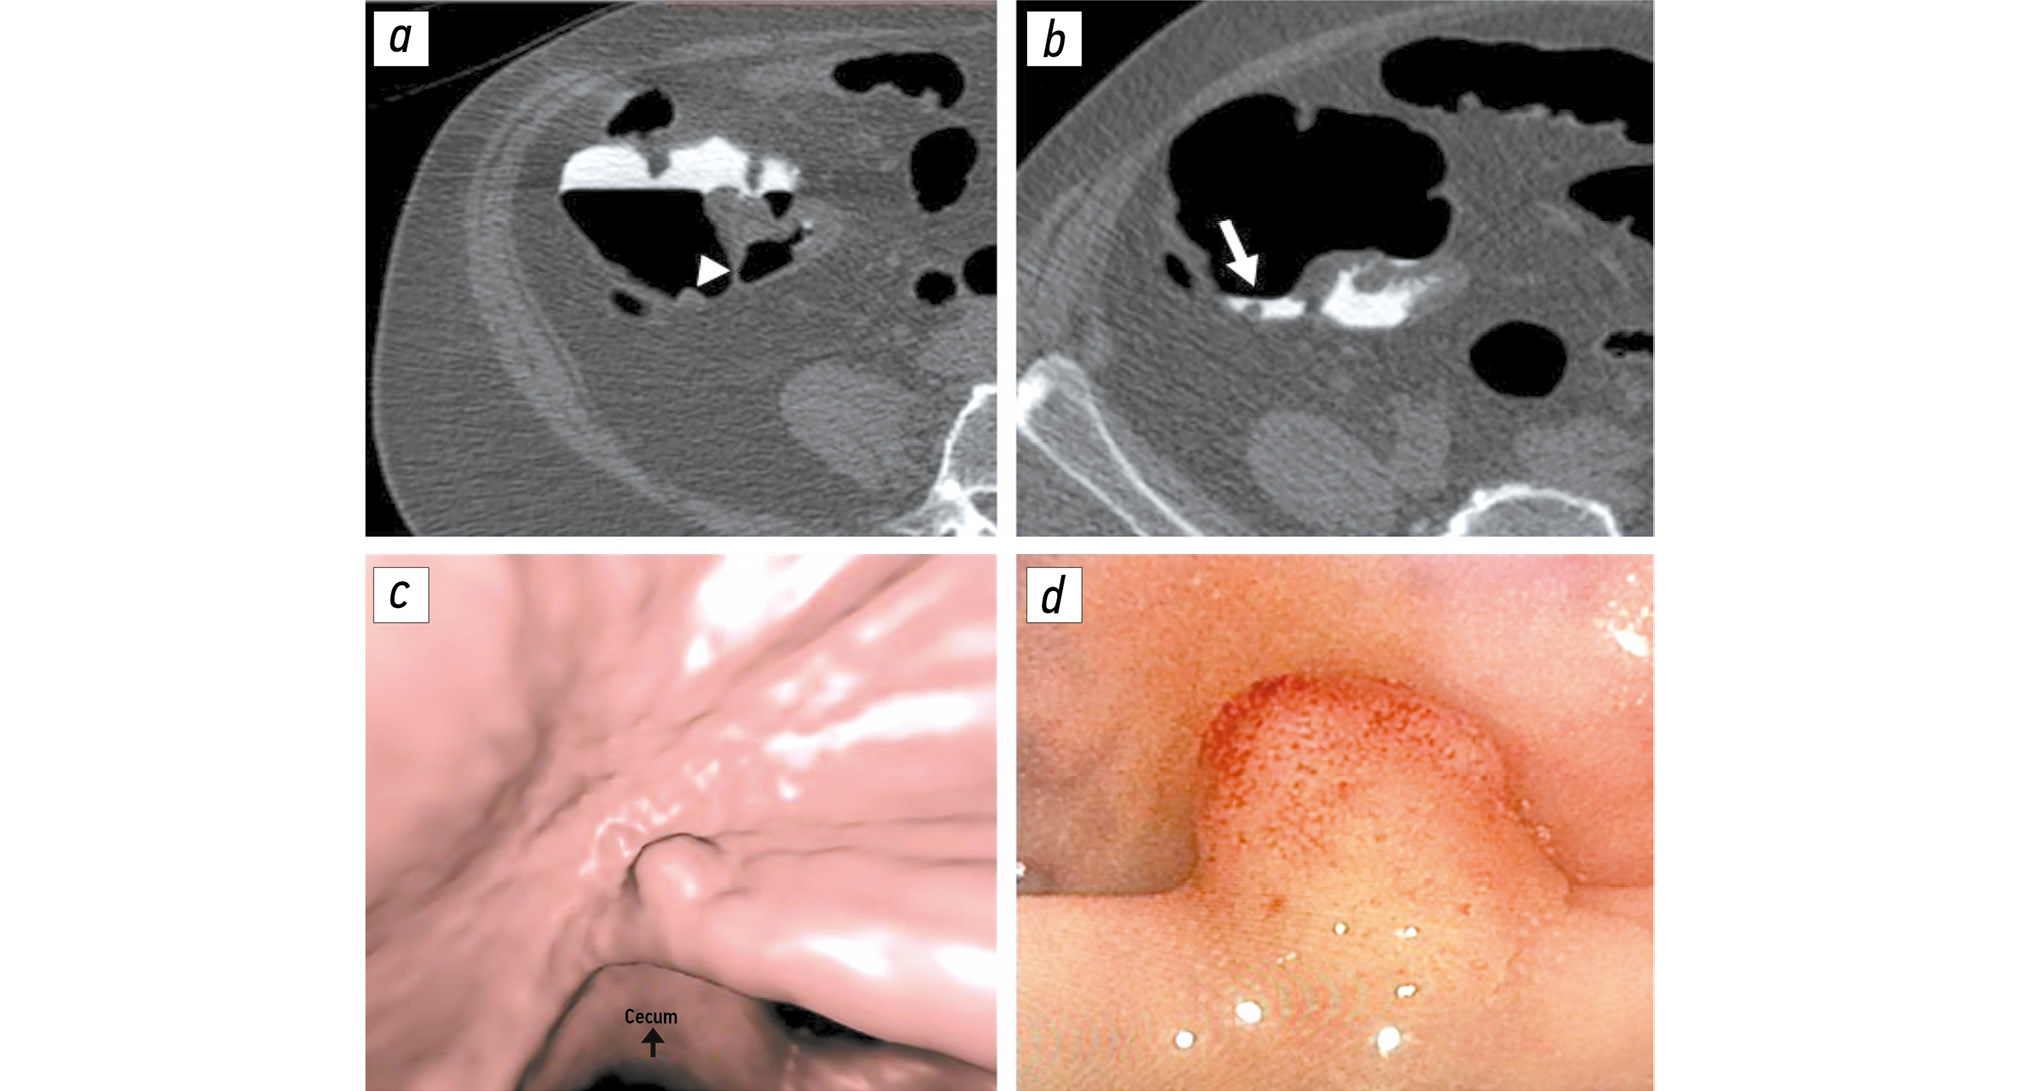

Comparison of single-dose and split-dose fecal tagging with iohexol in computed tomographic colonography

BACKGROUND: Proper fecal tagging allows for high-quality computed tomography colonography. However, there is no single tagging scheme. Therefore, the effects of a contrast enhancement regimen on fecal tagging should be evaluated.

AIM: This study aimed to compare the quality of single-dose fecal tagging with that of split-dose fecal tagging with iohexol during computed tomographic colonography and to assess the impact of these regimens on procedure tolerability.

METHODS: In this retrospective, selective, single-center study, the patients were divided into two groups based on whether they received single-dose (group 1) or split-dose (group 2) fecal tagging. Both groups received 50 mL of the iodine-containing contrast agent iohexol, with iodine concentration of 350 mg/mL. The residual liquid density was assessed using three parameters: maximum, minimum, and mean values. Additionally, the residual fluid homogeneity was assessed by calculating the mean standard deviation within the region of interest. Tolerability of preparation for colonography was assessed using a 10-point visual analog scale.

RESULTS: The final sample included 338 patients: 116 in group 1 and 222 in group 2. The mean, minimum, and maximum density values in group 2 were significantly higher than those in group 1: 943 [722; 1245], 753 [525; 1082], and 1079 HU [801; 1456] versus 681 [420; 907], 570 [374; 820], and 825 HU [496; 1154], respectively (p < 0.001). The residual fluid homogeneity was significantly higher in group 2 than in group 1: 59 [46; 78] versus 67 HU [54; 81] (р = 0.012). Group 2 showed a significantly lower subjective difficulty of preparation than did group 1: 4 [2; 6] and 5 [4; 7], respectively (p = 0.004).

CONCLUSION: A single dose of 50 mL of iohexol (iodine concentration: 350 mg/mL) provides higher-quality fecal tagging than a split-dose provides because of higher residual fluid density with maintained homogeneity. Moreover, single-dose tagging was found to be more tolerable.